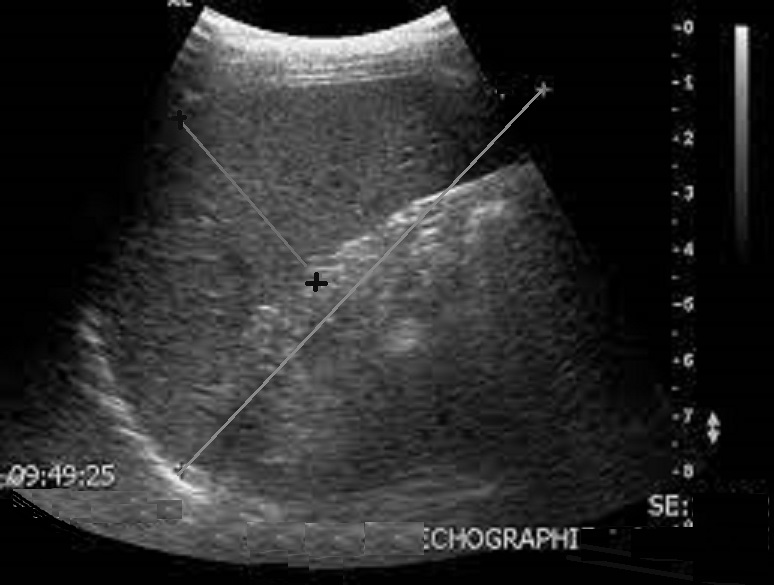

Normalement sur les

coupes longitudinals l'axe de la rate la diametre

longitudinale de la rate varie de 9,5 cm à 12cm ,

sa epais varie entre 4,5 - 6cm . |

Par la technique echographie en Doppler

on peut receceuillir image de artere et veine

splenique en couleur et peut en verifié par ;la

difference de sa pulse |